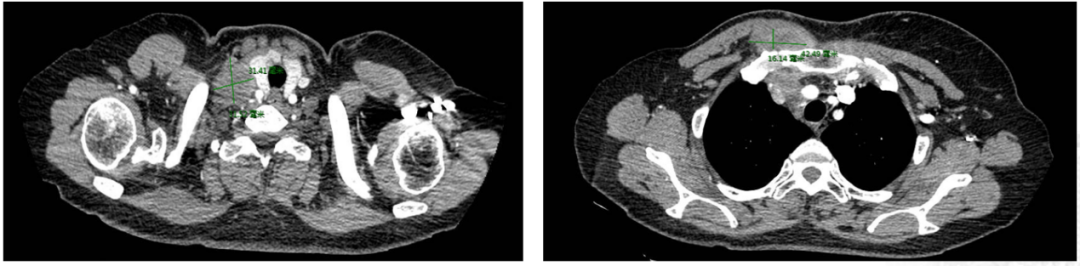

CT评估(右侧锁骨上区淋巴结):

CT评估(右胸壁):